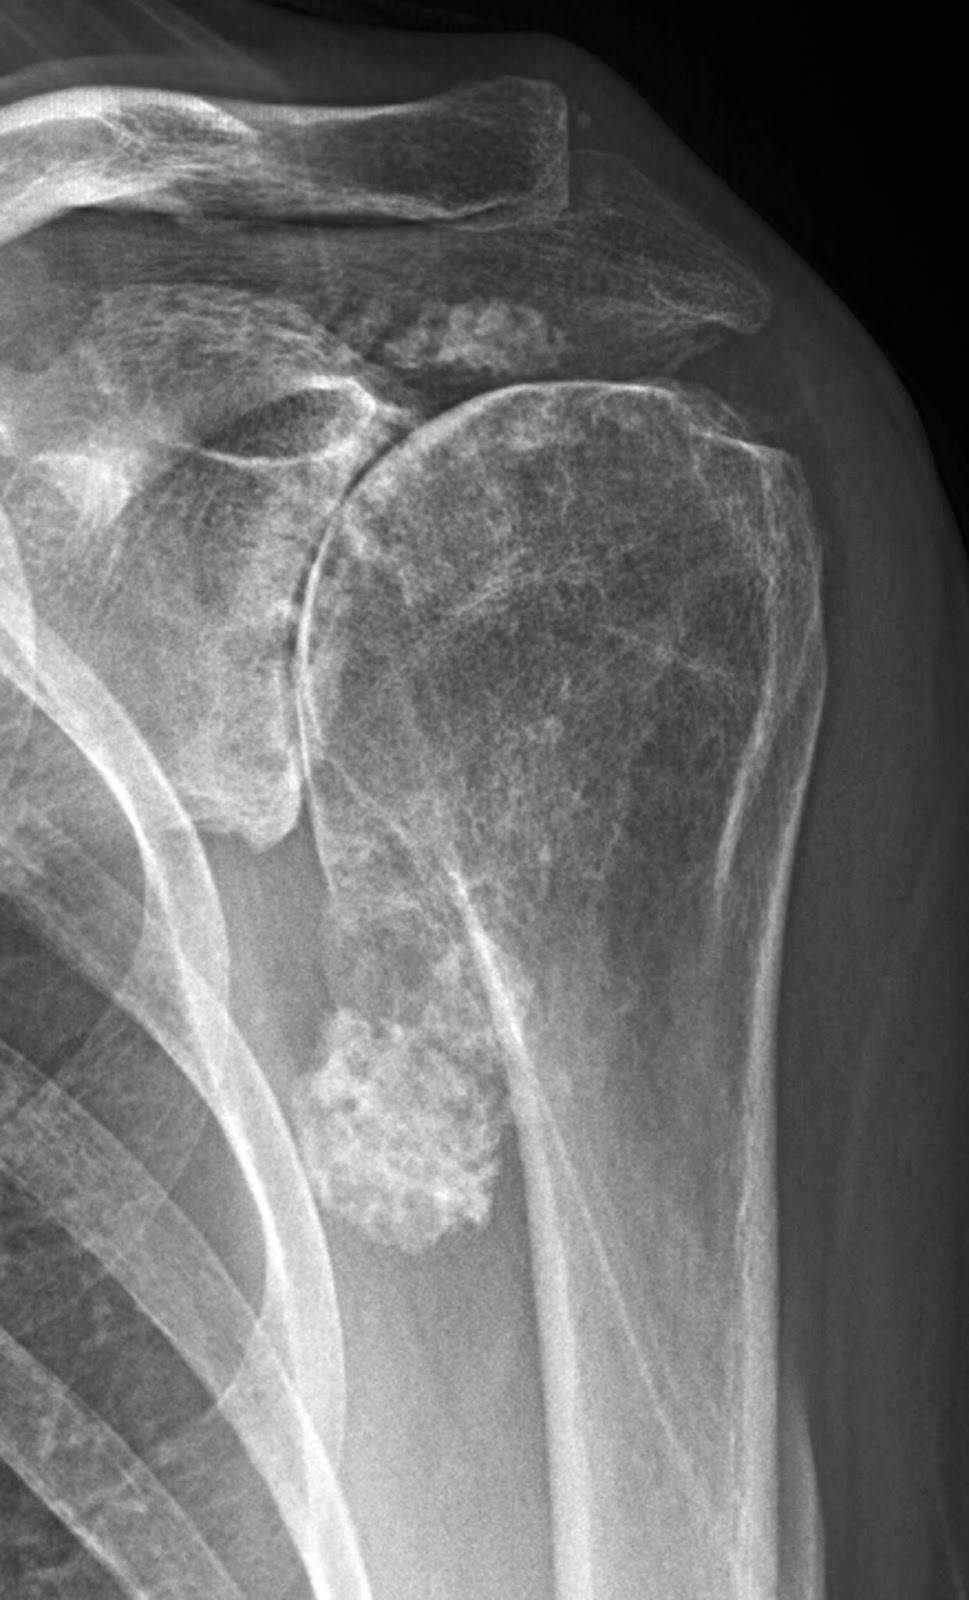

From www.sciencephoto.com

Osteoarthritis of the shoulder, Xray Stock Image C037/2760 Arthritis In Shoulder Burning Over time, you’ll notice a. symptoms of shoulder arthritis may include pain in the shoulder joint, stiffness and reduced range of motion. rheumatoid arthritis is a type of inflammatory arthritis which typically starts in the hands and feet, but can affect the shoulders. The following article will help you. infectious arthritis can affect the shoulders. in. Arthritis In Shoulder Burning.